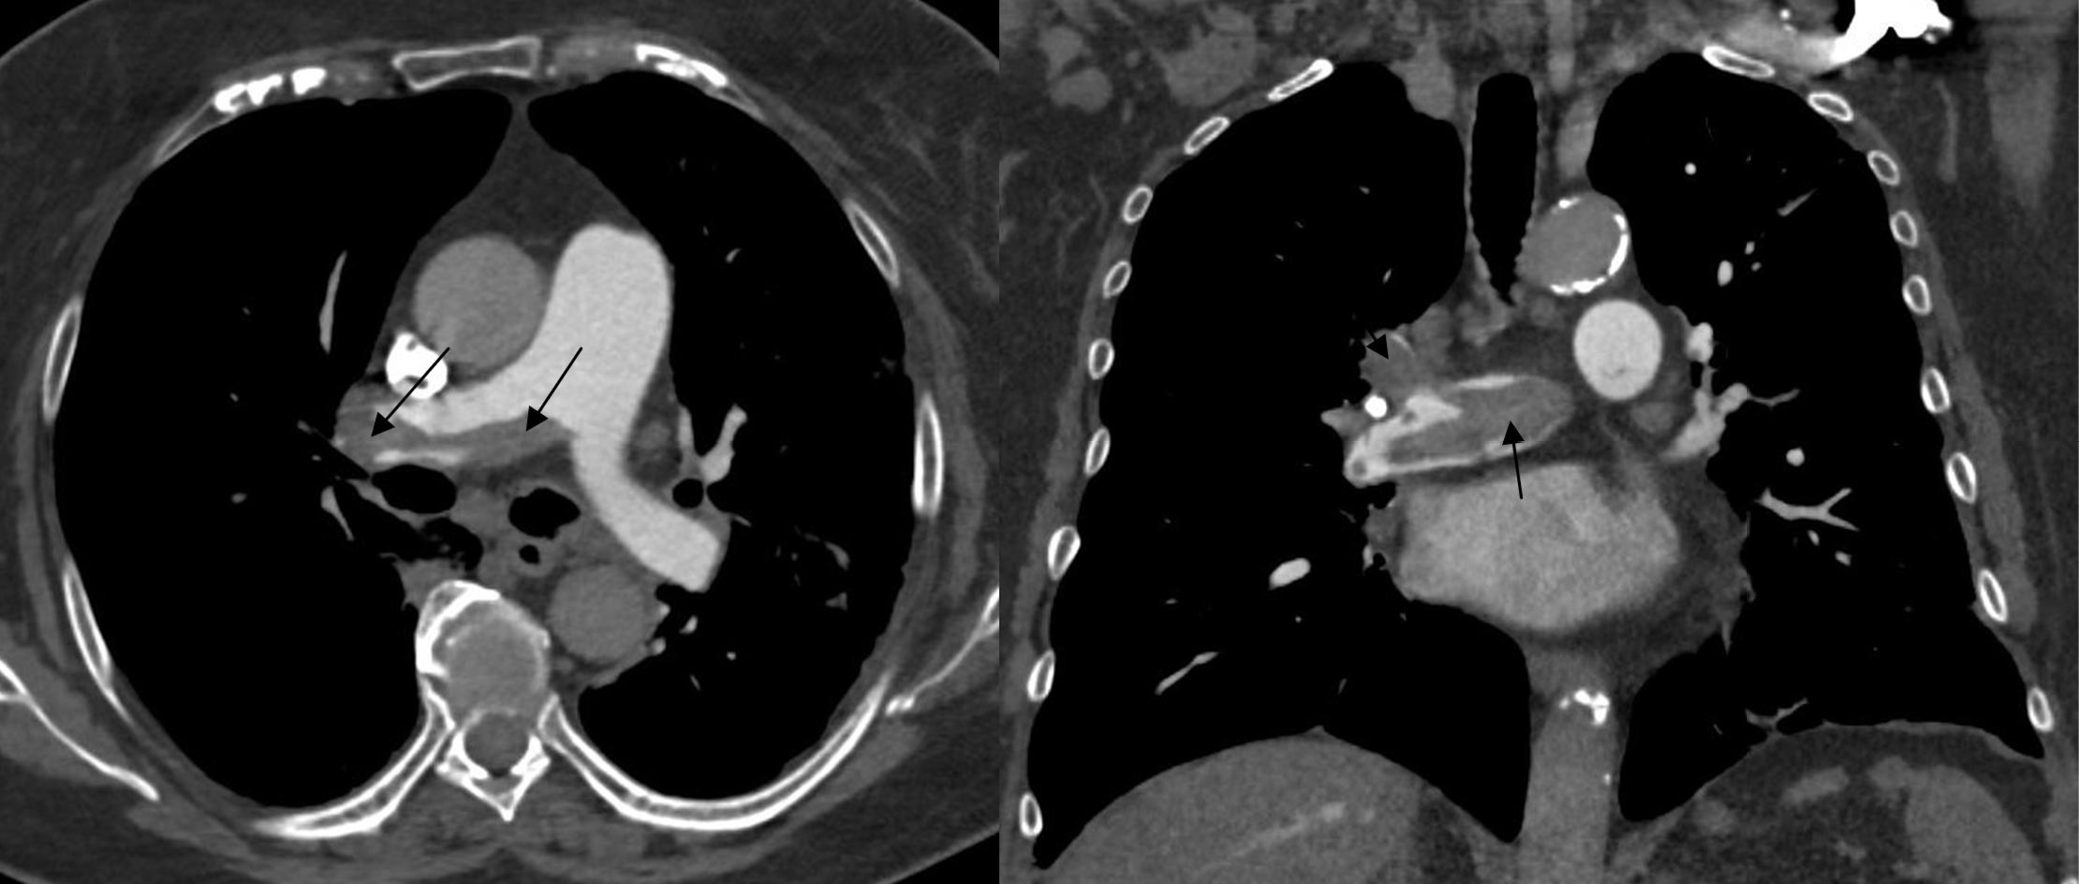

COVID-19 may result in a number of complications ranging from mild to very severe cases. It is estimated that 17–29% of patients develop acute respiratory distress syndrome (ARDS).6 Although the disease mostly affects the respiratory system, complications may influence any other system. Commonly reported sequelae are acute cardiac injuries. The mechanism of cardiovascular injury from COVID-19 has not been completely explained and could be a complex phenomenon. However, it manifests itself by myocardial ischemia and cardiac arrest. Recent works describe not only elevated troponin levels, but also myocardial ischemia and cardiac arrest associated with COVID-19 infection.25 The authors of the editorial entitled “Coronavirus disease 2019 (COVID-19) and the heart – Is heart failure the next chapter?” point to various cardiac complications after pneumonia.26 The diagnosis of cardiovascular disease (CVD) complications should be based on examination, symptoms, elevated cardiac markers, and electrocardiography (ECG). However, when the patient’s condition is not stable, further steps must be taken, including medical imaging27 (e.g., a CT scan28). A severe COVID-19 complication is myocarditis (Figure 7). Puntmann et al. suggest that approx. 60% of patients could experience myocardial inflammation, with no association to preexisting conditions or the severity of COVID-19.29 When myocarditis is suspected, the examination that should be taken into consideration is cardiac magnetic resonance (CMR).29 It is confirmed that SARS-CoV-2 infection increases the risk of pulmonary embolism (Figure 8) and deep vein thrombosis.30 When acute thromboembolic disease is suspected, not only should D-dimer levels be tested, but an assessment via computed tomography angiography (CTA) is essential.31